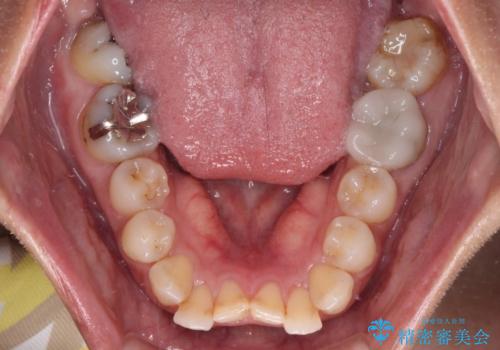

【モニター】処置歯の多い歯列 インビザラインでデコボコを整える

- 上下前歯のデコボコを気にして来院された患者様です。

歯列としては、ワイヤー装置でもインビザラインでも、どちらでも対応可能でしたが、処置されている歯が多く、ワイヤー装置を装着するためには処置歯のやり直しが必要な状態でした。

インビザラインでもアタッチメントを装着できないという同様のデメリットがありますが、比較的矯正治療を行いやすい歯列であったので、インビザラインによる矯正治療を行うこととしました。